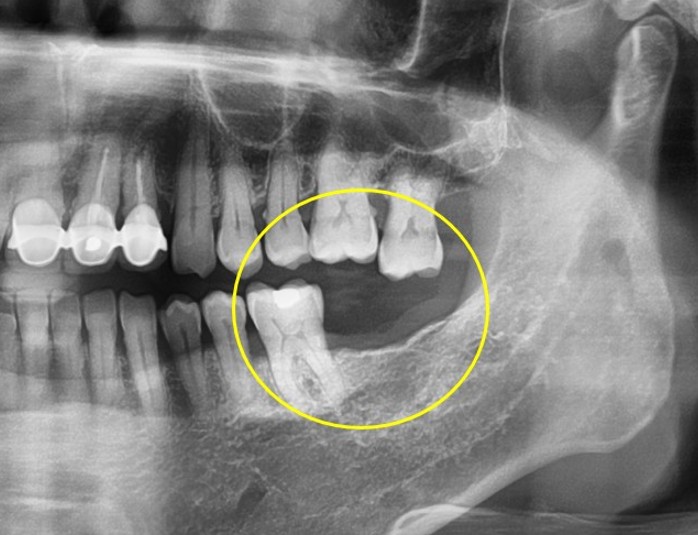

임플란트/틀니